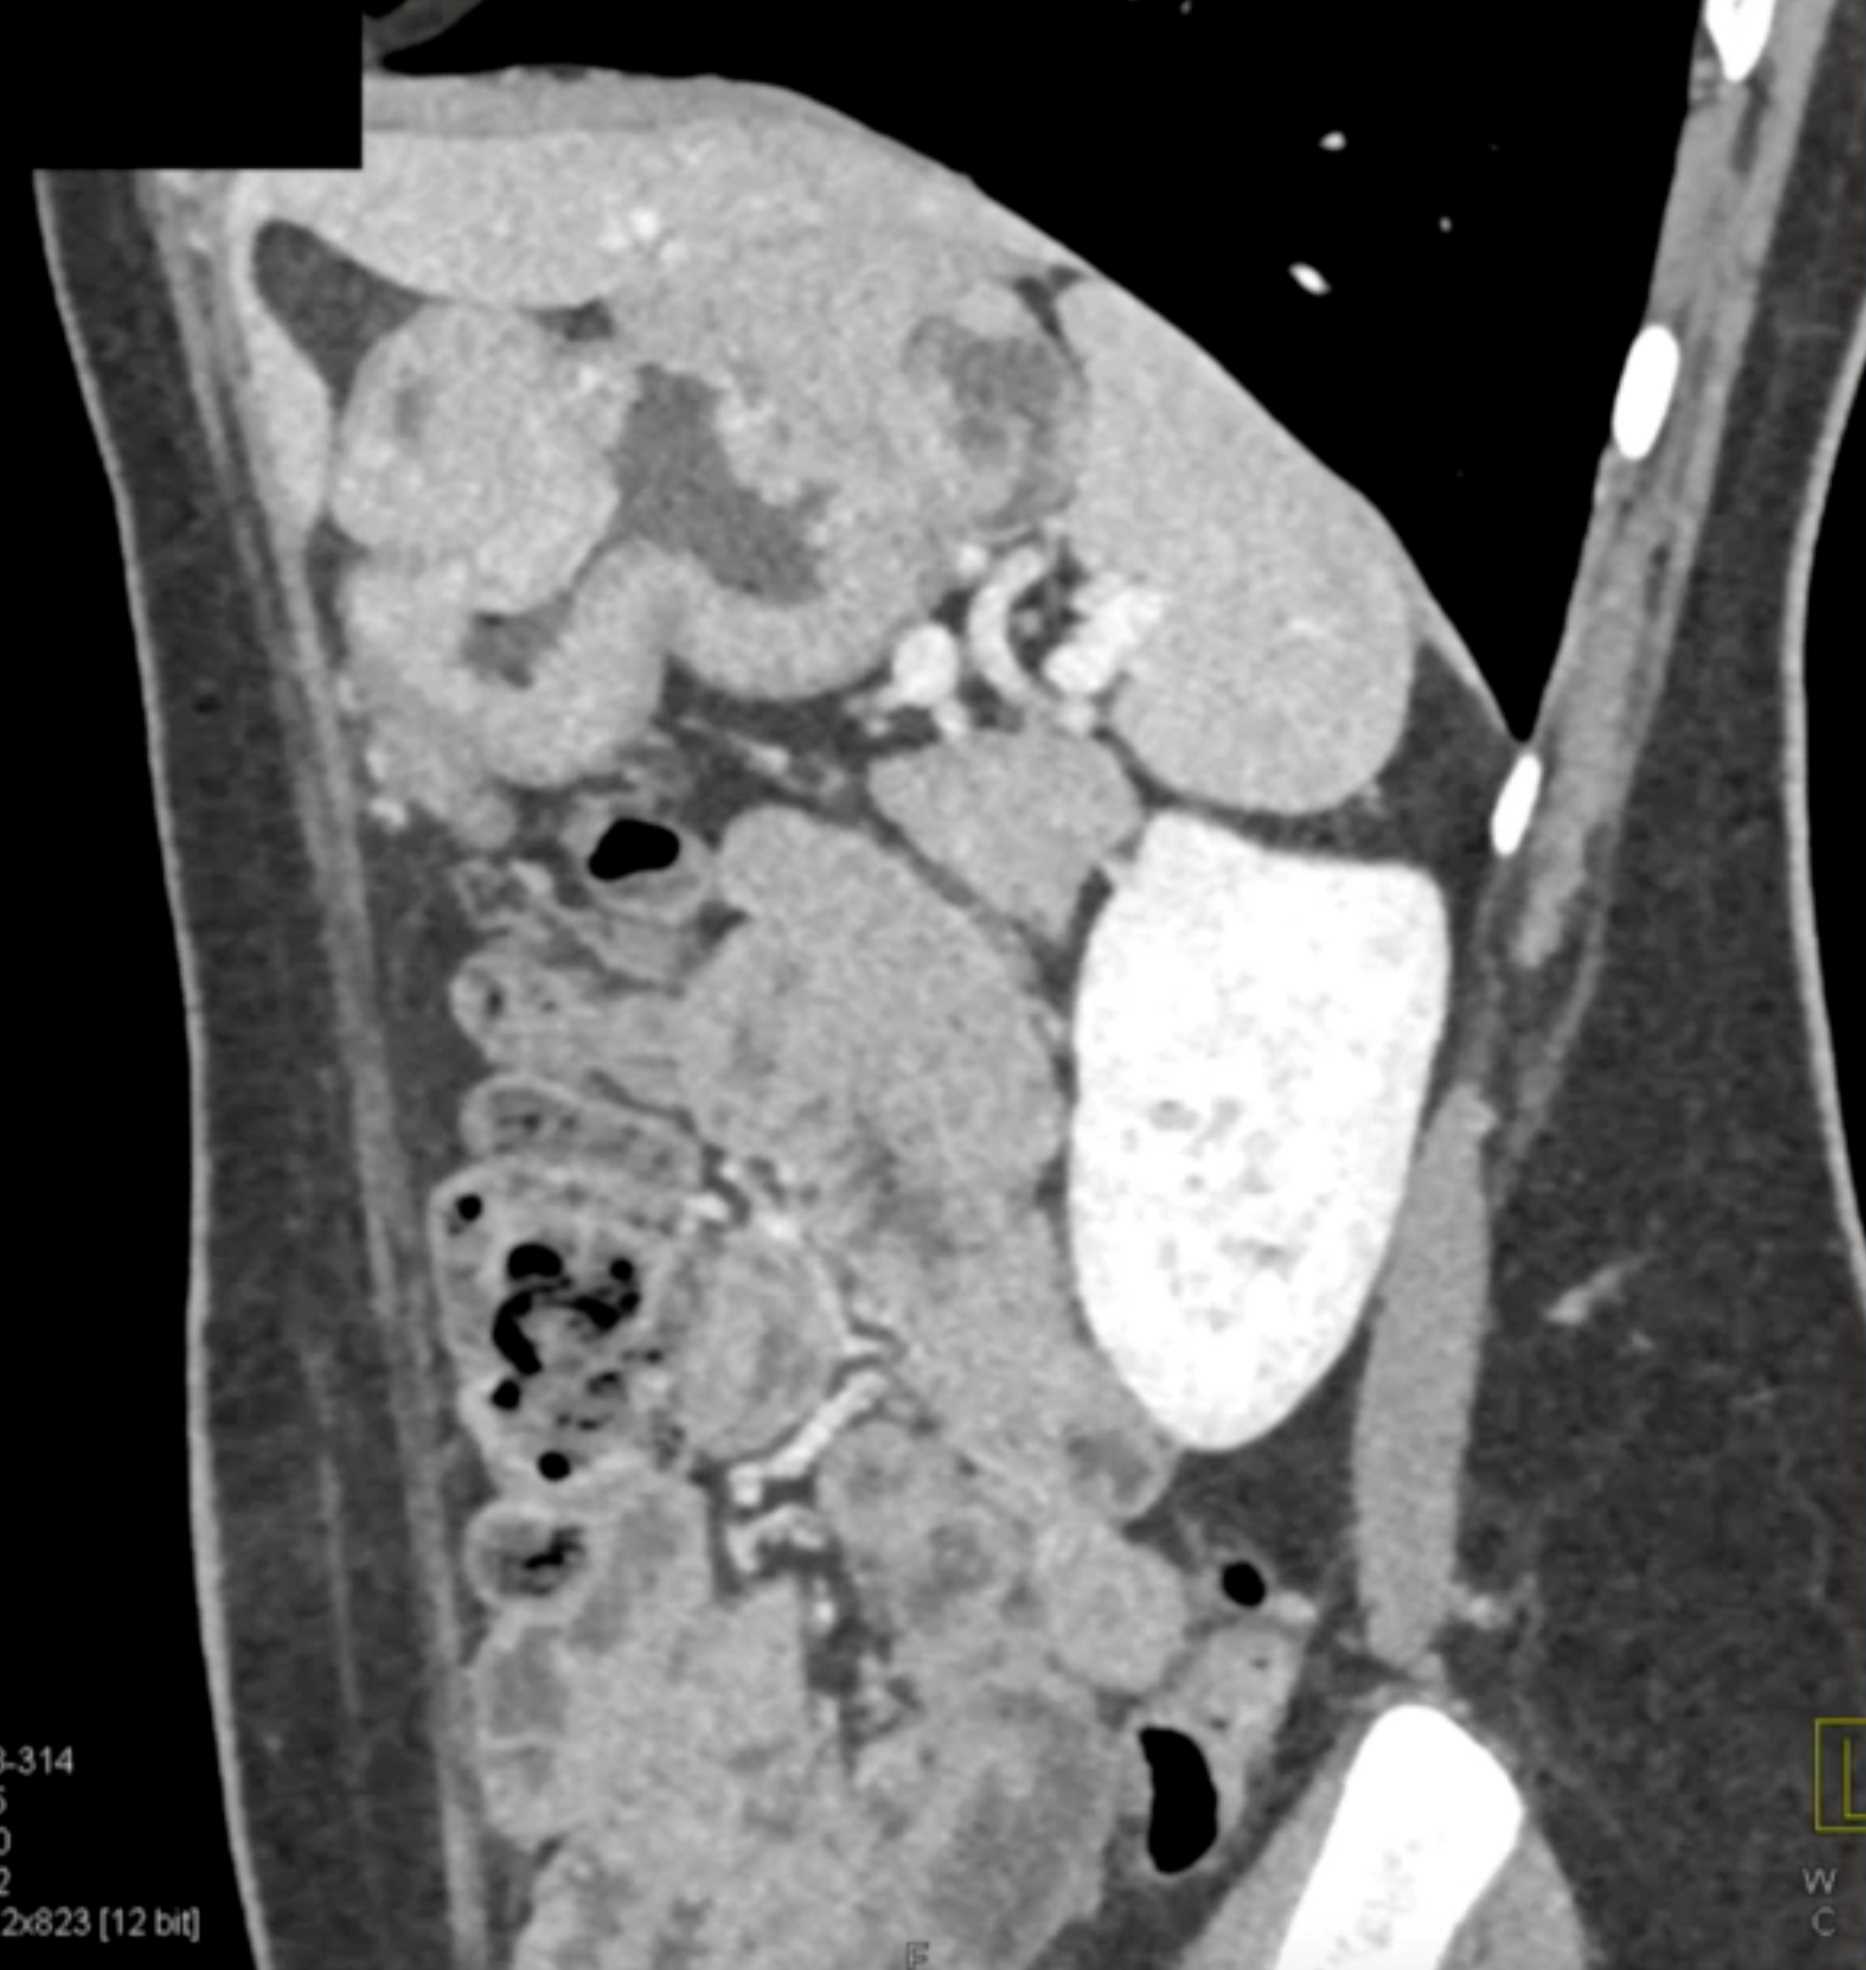

Multiple Gastric GIST Tumors with Spread to Nodes (Carney-Stratakis Syndrome)